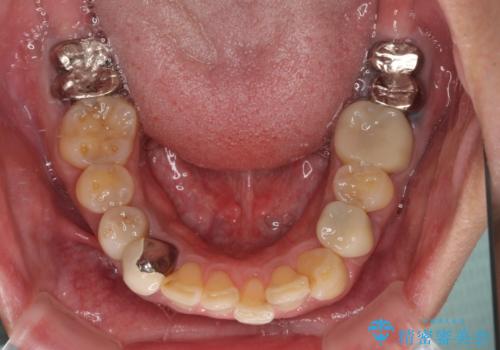

- 近医にて下顎奥歯の抜歯が必要と言われたとのことで来院された患者様です。

診察の結果、奥歯は左右ともに抜歯が必要な状態でした。

他の銀歯も気になっており、セラミックにしたいとの要望があり、詳しくお話をすると、デコボコの歯ならびも整えたいとのことでした。

抜歯が必要な歯は事前に抜歯をし、その後ワイヤー装置にて歯列矯正を行い、途中でインプラントを埋入し、オールセラミッククラウンにて補綴治療を行うこととしました。